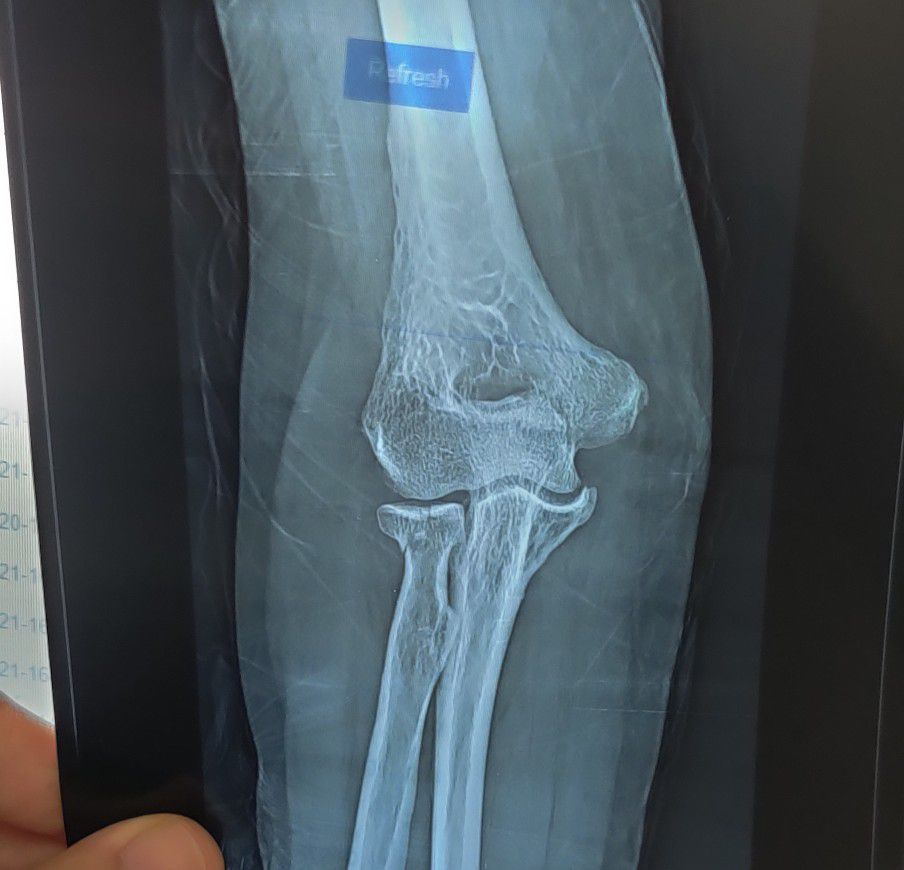

Radius Fx

Fracture

Ortho

Radius